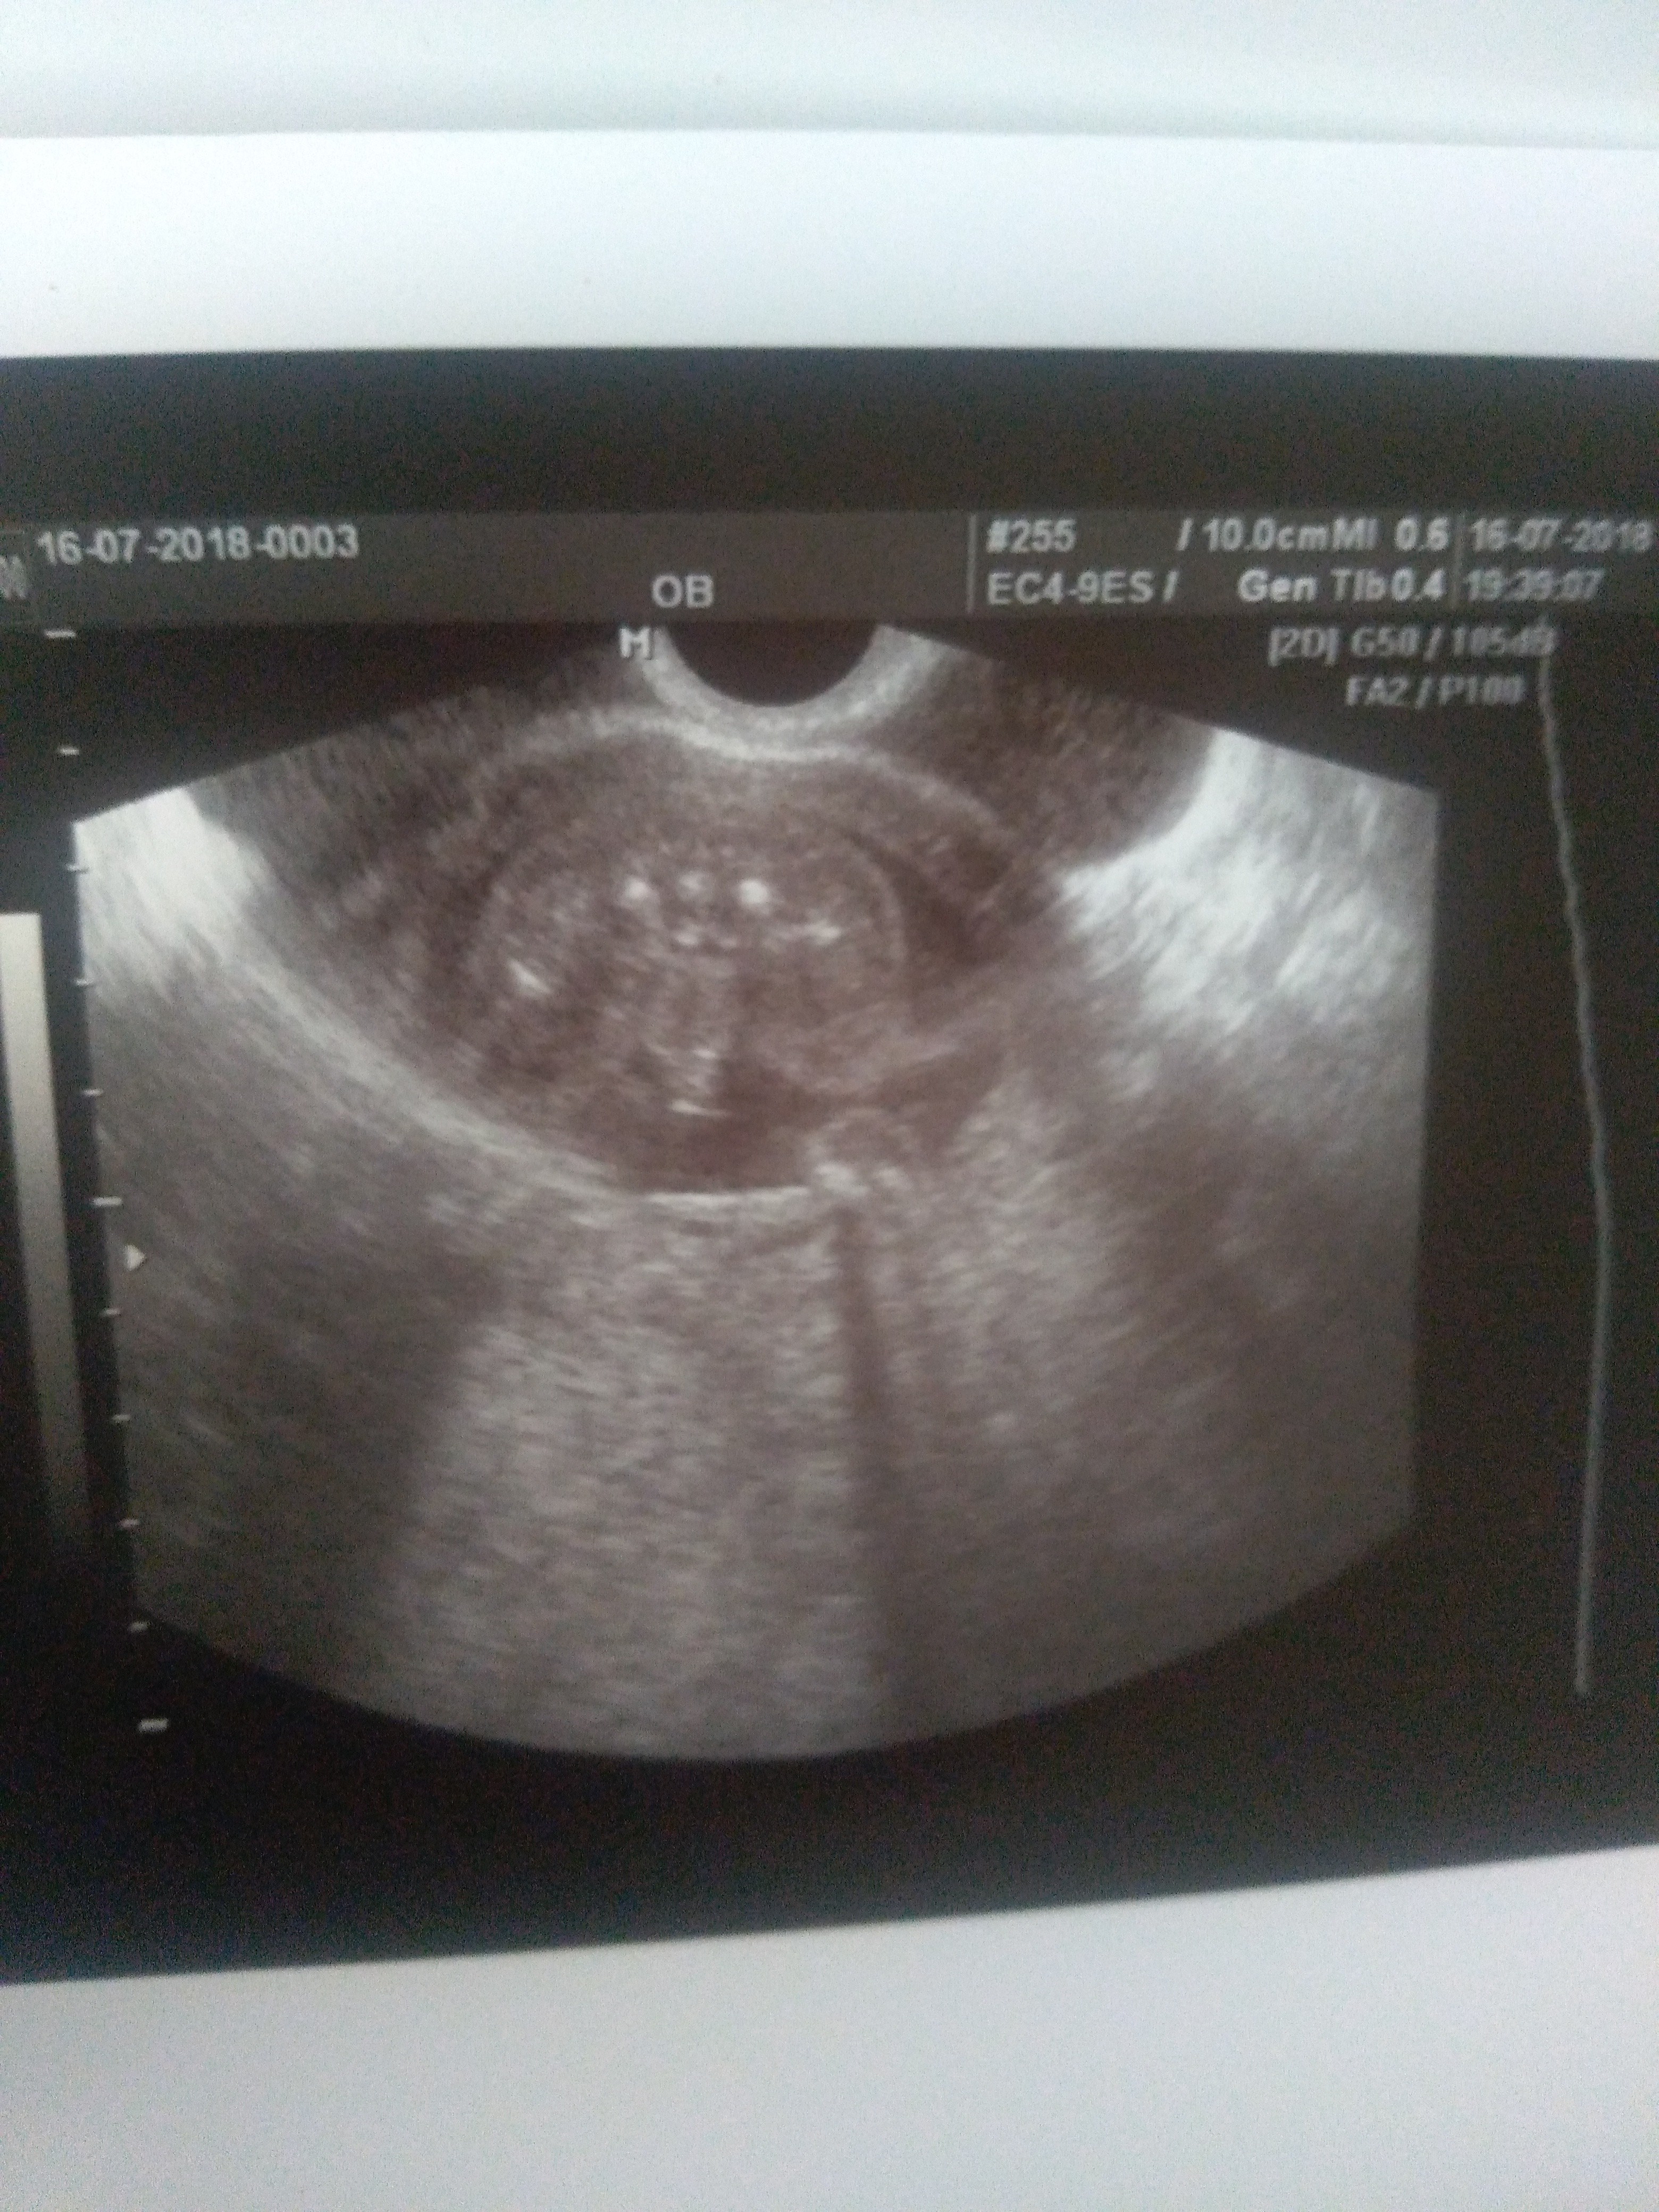

Witam w 19 tygodniu ciąży dowiedziałam się ze będę miała dziewczynkę w 20 tyg okazało się jednak , że to chłopak. Sama już nie wiem bo na jednym usg widać na pewno dziewuche a na drugim chłopca. Może to pempowina ?? Może ktoś mi pomoże rozwiązać ta zagadkę

• 4A8F5FF1-76CA-4DE0-AC12-5EDF08E820F2.jpg

4A8F5FF1-76CA-4DE0-AC12-5EDF08E820F2.jpg

596,4 KB · Wyświetleń: 23 774